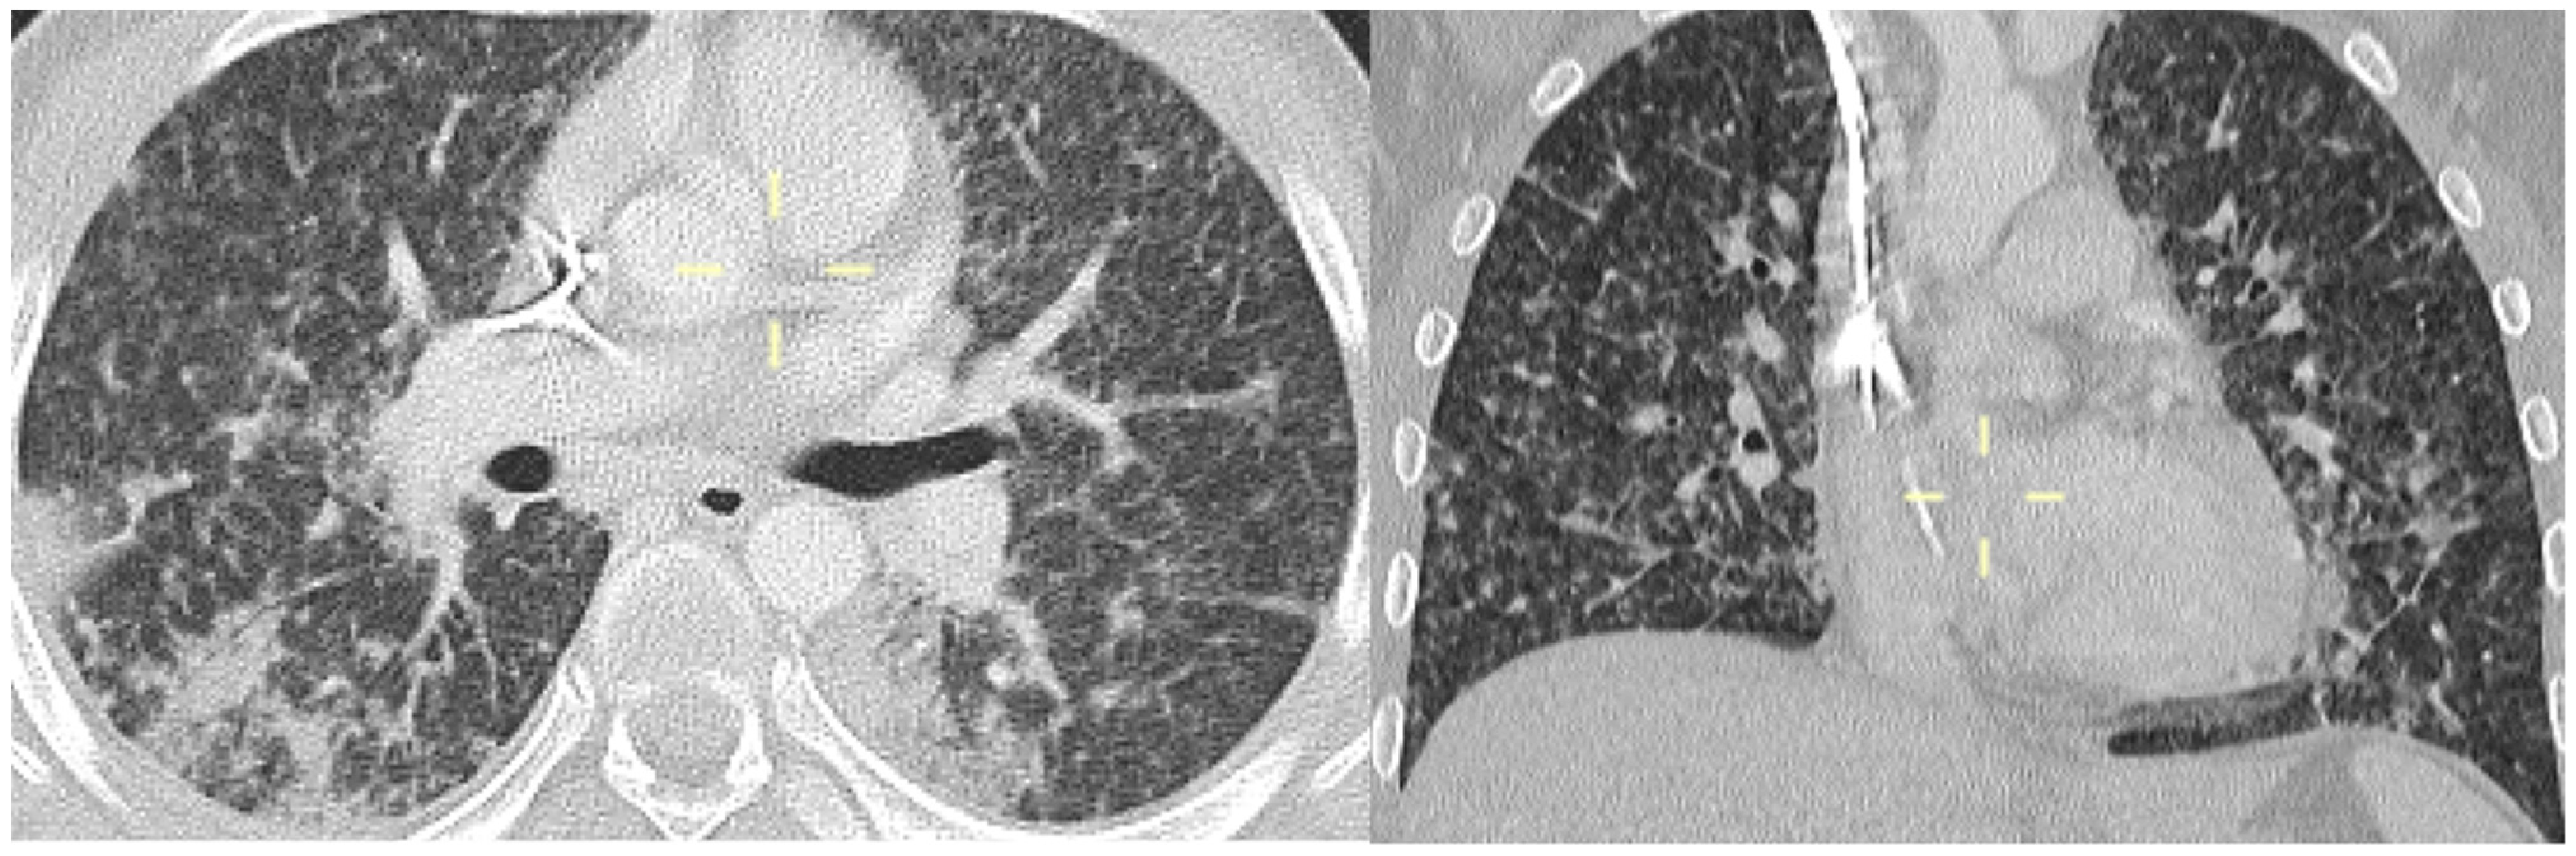

3.5. Radiological Features of PJP in the Study Population